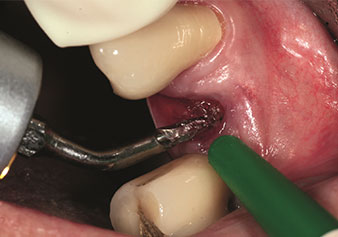

One application, which is often underestimated is the atraumatic extraction of tooth roots or root fragments in the scope of alveolar management. The fine periotomes, which are currently available in two versions (EX1 and EX2 from W&H), can also be used to remove teeth which have previously undergone special endodontic treatment or ankylosed roots with ease. This results in extraction alveoli where both the hard and soft tissue are fully intact as it is generally possible to avoid reflection.

This establishes the optimal basis for subsequent or immediate implant treatment (Figures 1 and 2 included with the kind permission of Dr Torsten Conrad, Bingen a. Rhein).

Fine periotome (EX1 instrument)

Fig. 1: Fine periotome (EX1 instrument).